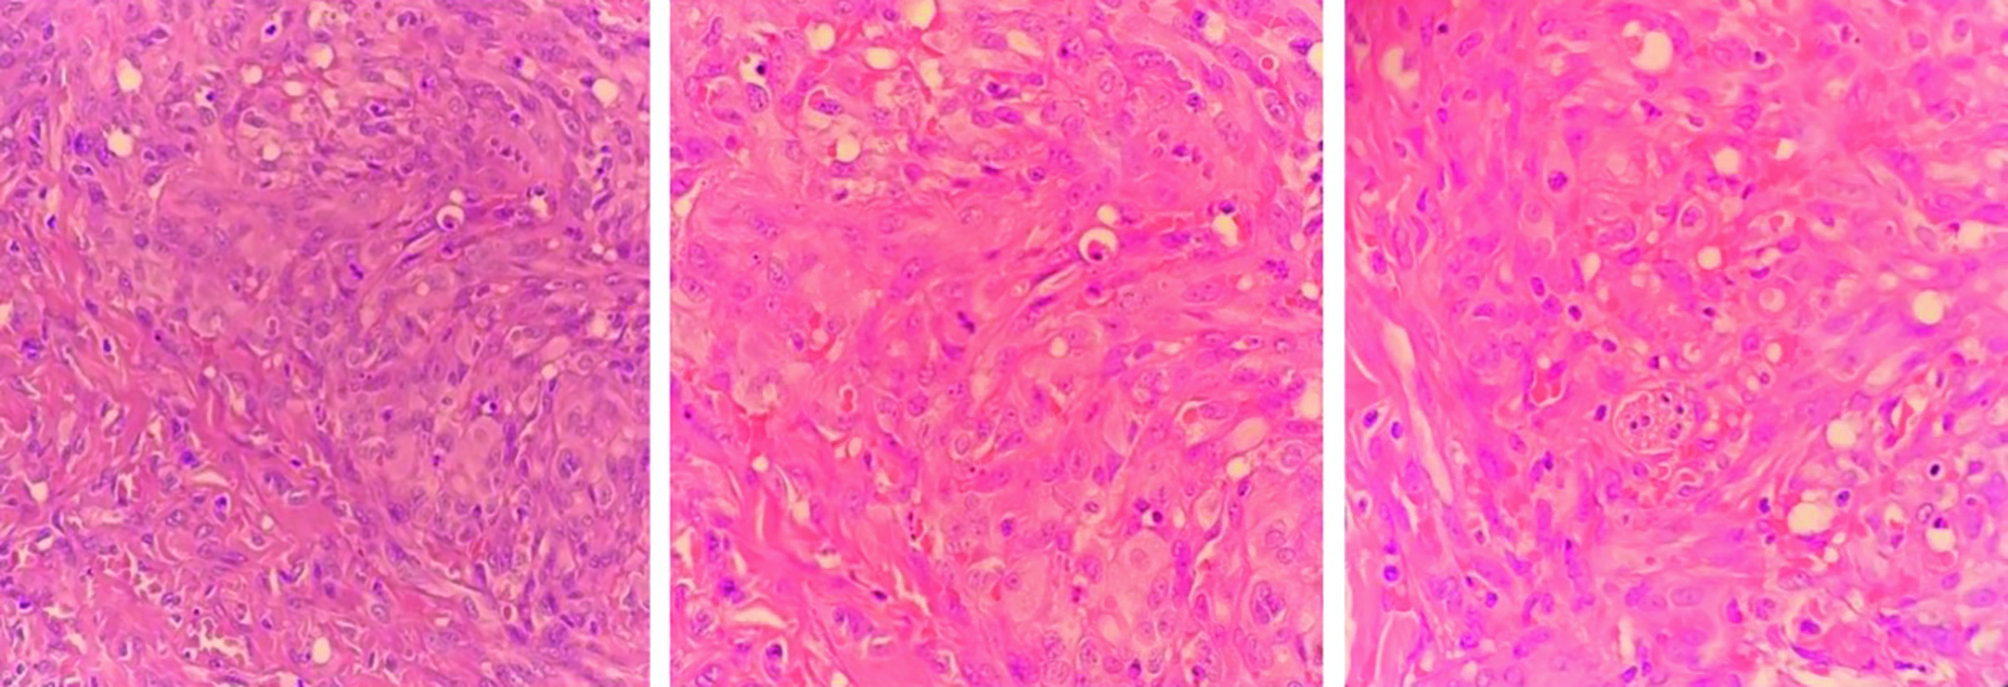

Пациенту выполнена биопсия патологических элементов на теле. При гистологическом исследовании морфологическая картина соответствовала СК (рисунок 2). При иммуногистохимическом исследовании выявлены ядерная гранулярная экспрессия HHV-8, экспрессия ERG, Fli1, фактора VIII, подопланина, CD34, негативная реакция с PanCK, 0D31. По данным вирусологического исследования биоптата кожи, жидкости бронхоальвеолярного лаважа и крови методом полимеразной цепной реакции обнаружена ДНК HHV-8. На компьютерной томографии (КТ) органов грудной клетки, брюшной полости отмечается патологическая специфическая инфильтрация обоих легких (рисунок 3).

Рисунок 2. Гистологическая картина: опухолевая ткань располагается в виде пучков и узлов среди волокон коллагена. Клетки овоидной и веретеновидной формы с обильной эозинофильной цитоплазмой и крупными овоидными ядрами с гранулярным хроматином. Отмечается формирование клетками мелких вакуолей, которые заполнены эритроцитами. Видны множественные депозиты гемосидерина

Figure 2. Histological findings: the tumor tissue is arranged in bundles and nodules among collagen fibers. The cells are ovoid and spindle-shaped with abundant eosinophilic cytoplasm and large ovoid nuclei containing granular chromatin. The tumor cells are seen to form small vacuoles filled with erythrocytes. There are numerous hemosiderin deposits

Следует отметить, что HHV-8 изменяет дифференцировку инфицированных эндотелиальных клеток в лимфатические эндотелиальные клетки и индуцирует аберрантную экспрессию мезенхимальных маркеров. Таким образом, веретенообразные клетки опухоли могут демонстрировать маркеры как эндотелиальной, так и мезенхимальной дифференцировки. Данный феномен определяется как эндотелиально-мезенхимальный переход (endothelial-to-mesenchymal transition) [15, 16]. Активация путей STAT3 и Akt, индуцируемая вирусным IL-6, усиливает лимфатическую трансформацию эндотелия [17]. Это сопровождается повышенной инвазивностью, миграцией, продукцией ангиогенных цитокинов (VEGF, Ang2, IL-6, IL-8) и типичными гистологическими признаками (аномальные сосуды, экстравазация эритроцитов, воспалительный инфильтрат) [18-20]. Описанные выше гистологические особенности наблюдались и у нашего пациента.